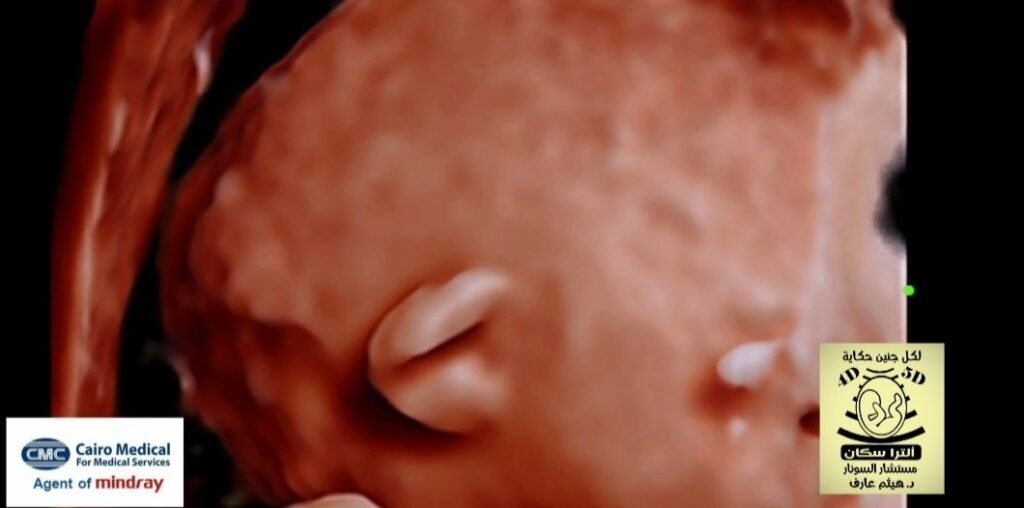

Low set ear 👂 with microtia in trisomy 21 fetal ultrasound

low-set ears (LSE) and microtia (underdeveloped external ear) are common findings in individuals with Trisomy 21 (Down Syndrome) and are often associated with hearing loss, so early audiological evaluation is crucial for timely intervention, with LSEs serving as a potential marker for chromosomal anomalies.